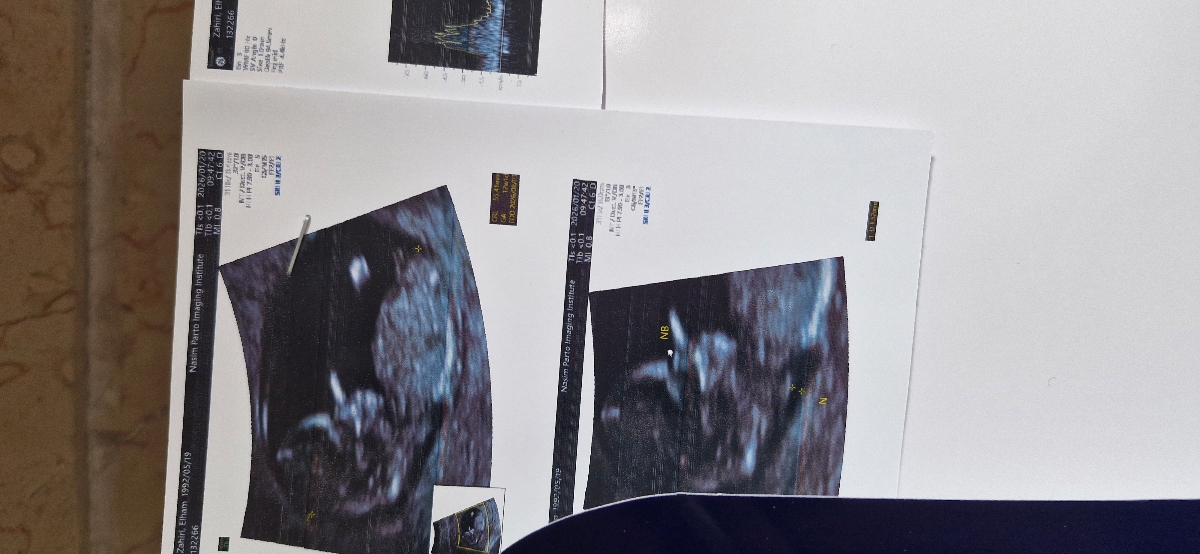

ممنون میشم سونو ان تی منو تفسیر کنید🙏

خداروشکر همه چیز عالی است و مشکلی ندارد البته جهت تفسیر صحیح باید منتظر بخش خون غربالگری باشیم

میوم دیده شده نیز اهمیت ندارد صرفا در سونوگرافی ها باید تحت نظر باشد